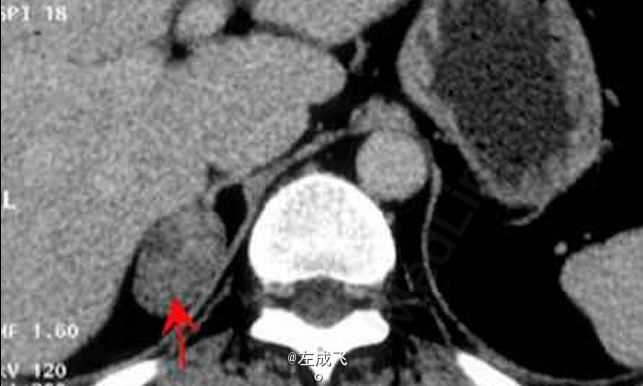

患者体检时偶尔发现右肾上腺区肿块,无其他明显症状 辅查CT,平扫示右肾上腺类圆形肿块,边界清楚;增强扫描呈不均匀强化